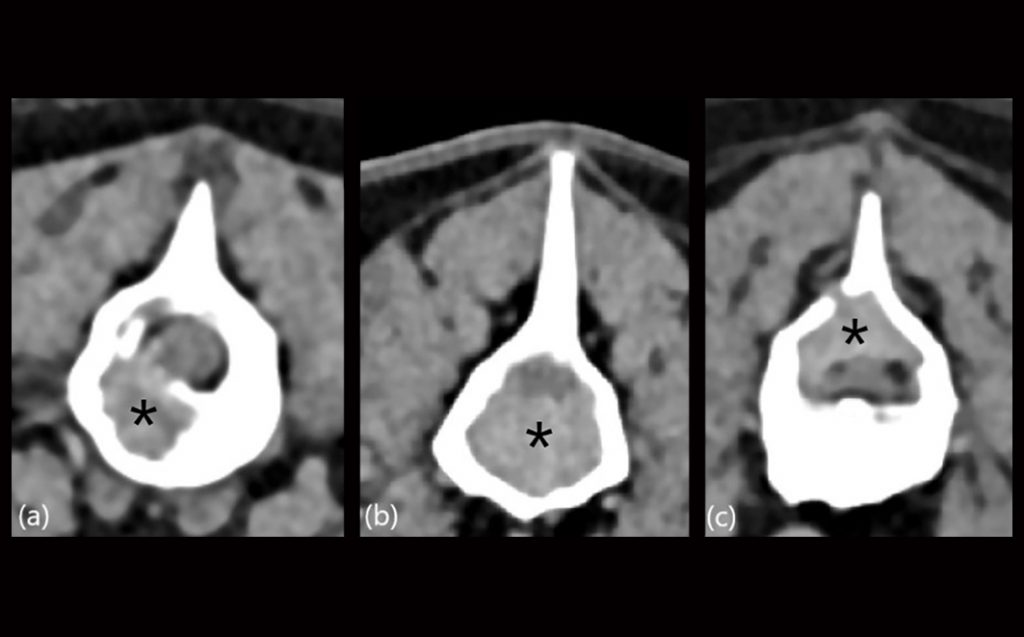

A contribuição da tomografia computadorizada, ultrassonografia ao modo-B, doppler colorido e contraste de microbolhas na avaliação de lesão focal hepática em cães – revisão de literatura e relato de caso